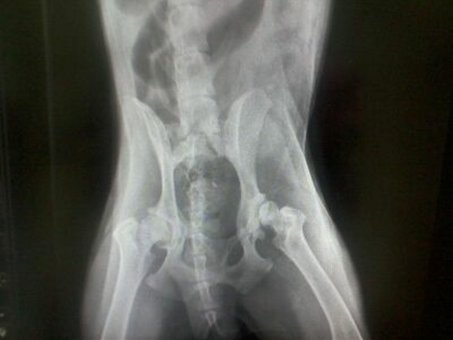

Sąnarių problemos - 2: Displazija, degeneracija